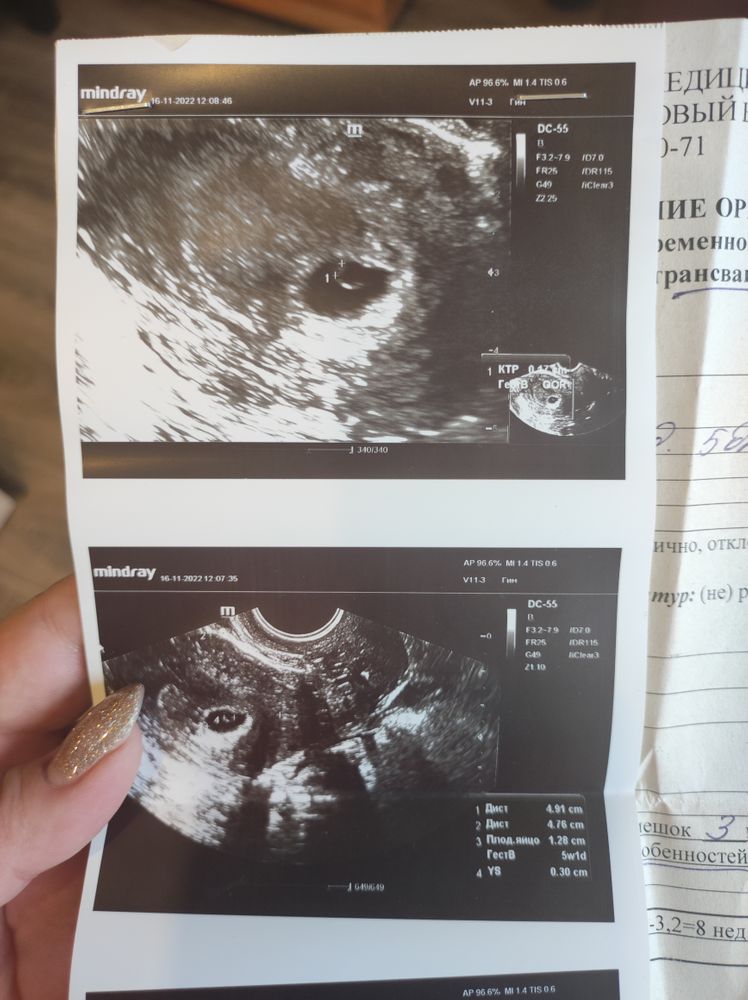

Первое УЗИ 21дпп😍

9 недель беременности 🤰🏻🙏 20 дпп все на месте❤️